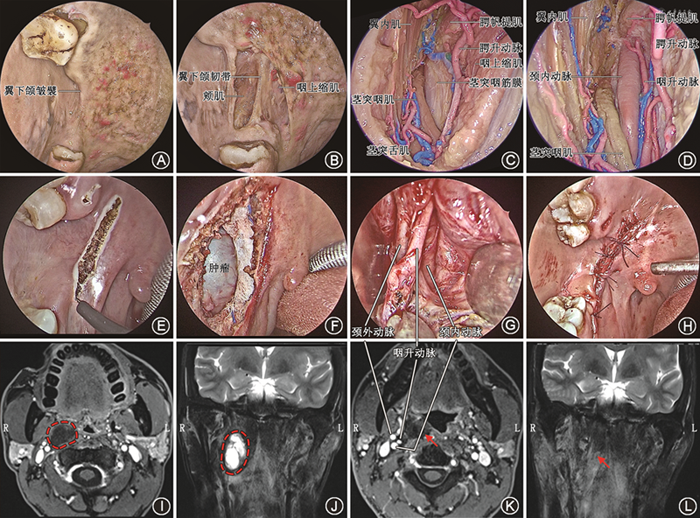

内镜经口入路侧颅底手术中,如果出现颈内动脉裸露、脑脊液漏等,需要进行侧颅底修复。特别是有过放疗病史的患者,建议使用带血管蒂的组织瓣保护裸露的颈内动脉及侧颅底骨质。对于鼻咽癌放疗后的患者,无论复发还是放射性骨坏死,其鼻咽颅底周围由于放射性损伤均可能导致局部缺血、炎症,不利于术后的创伤性修复;若术后出现骨炎、化脓,则有可能造成颈内动脉破裂大出血。使用带血管蒂的组织进行修复可增加侧颅底缺损区域的血供,加快创伤修复,减少进一步坏死的可能性,最大程度地保护颈内动脉,降低术后致死性颈内动脉大出血概率。在内镜经口颅底手术中,我们推荐使用颏下瓣[7]、颞肌瓣、鼻中隔黏膜瓣等进行修复。

2. 术前检查与颈内动脉预处理:术前应行增强CT和增强MRI检查,如果肿瘤累及颈内动脉或颅内,可选择在复合手术室进行手术。复杂性侧颅底肿瘤手术需要多学科诊疗团队成员协同参与,建议邀请神经外科和介入科医生参与手术。应常规进行颈内动脉球囊闭塞试验(balloon occlusion test,BOT),评估阻塞患侧颈内动脉后脑侧支的循环代偿功能[11]。对于肿瘤与颈内动脉尚可分离的患者,可在DSA护航下手术。对于肿瘤与颈内动脉无法分离的患者,如果BOT阴性,可以考虑颈内动脉栓塞;如果BOT阳性,需要先行颅内外血管搭桥,再行颈内动脉栓塞,或置入颈内动脉覆膜支架。

3. 手术策略:根据病变位置选择合适的切口。若病变主体位于中线的鼻咽区、咽鼓管区,可采用内镜经口经腭入路;若病变主体位于侧方的神经血管区、颞下区,可采用内镜经口经翼下颌皱襞入路;若病变广泛侵犯颅底中线区域和侧方区域,可采用内镜经口经翼突后入路。无论采用何种入路,都应采用广暴露的原则,尽可能大范围地显露周围重要结构,如颈内动脉、颈内静脉、后组颅神经等。广暴露的目的是充分保护好这些结构,术后根据颅底缺损的大小进行妥善修复。与内镜经鼻颅底手术相比,内镜经口侧颅底手术应注意伤口愈合不良导致的腭瘘,建议术中对切口分层缝合,术后鼻饲饮食以避免经口饮食造成的伤口感染。